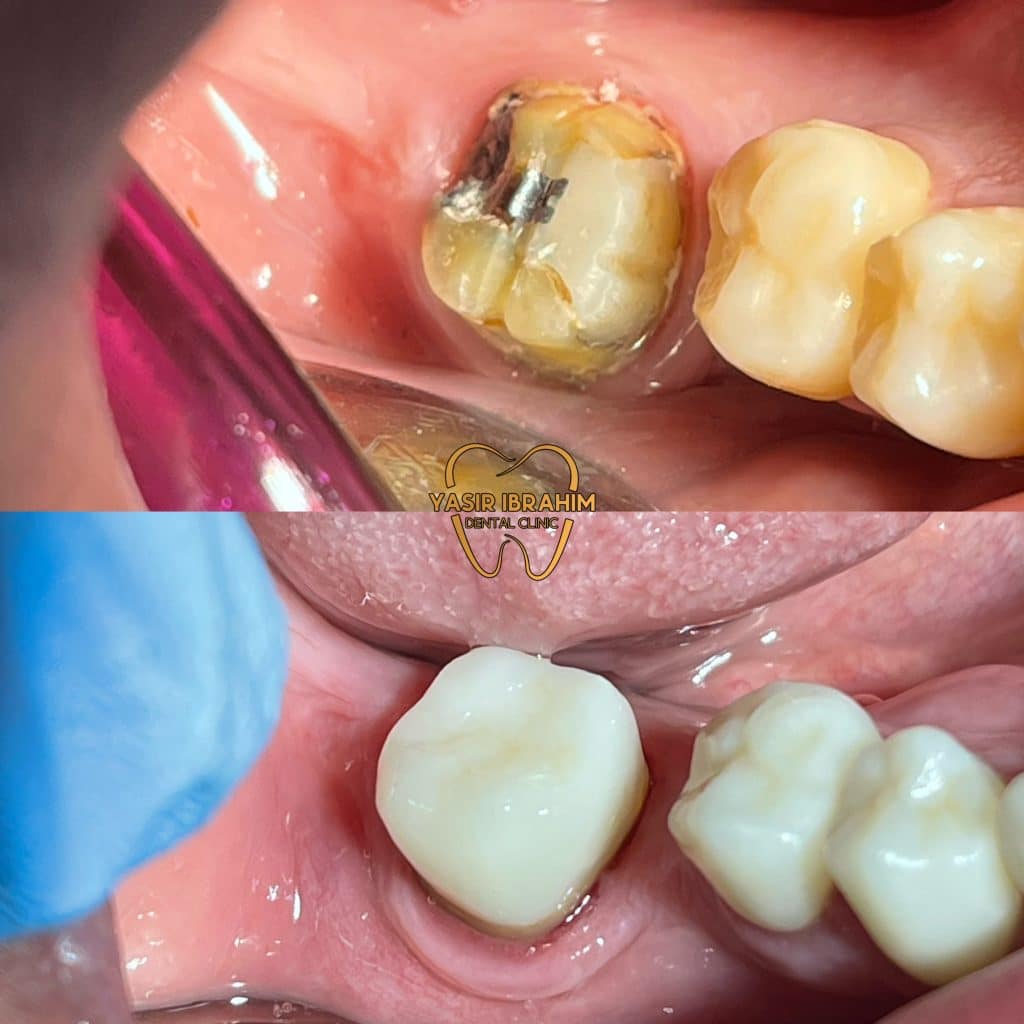

1_remove the crown .

3_build up by use ribbond and ever X

4_cover the tooth by endocrown .

The ribbond is placed in a circumferential manner to strengthen the walls of the tooth and protect it from fracture.

EVER X.

tooth build up.

Tooth prep for endocrown with ferrule design.

ips e.max press.

Marginal adaptation.

endocrown cementation .